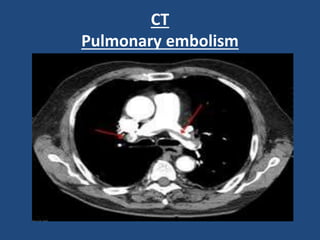

4-CT:

(Triple rule out, CT aortography, CT pulmonary

Pulmonary embolism